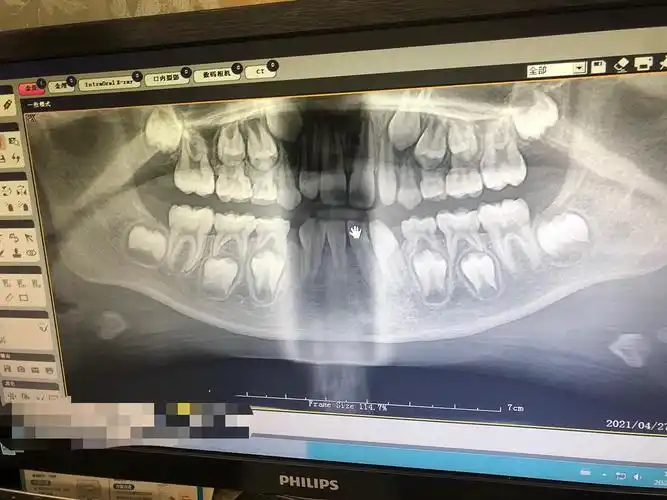

新鲜de乳牙萌发全景